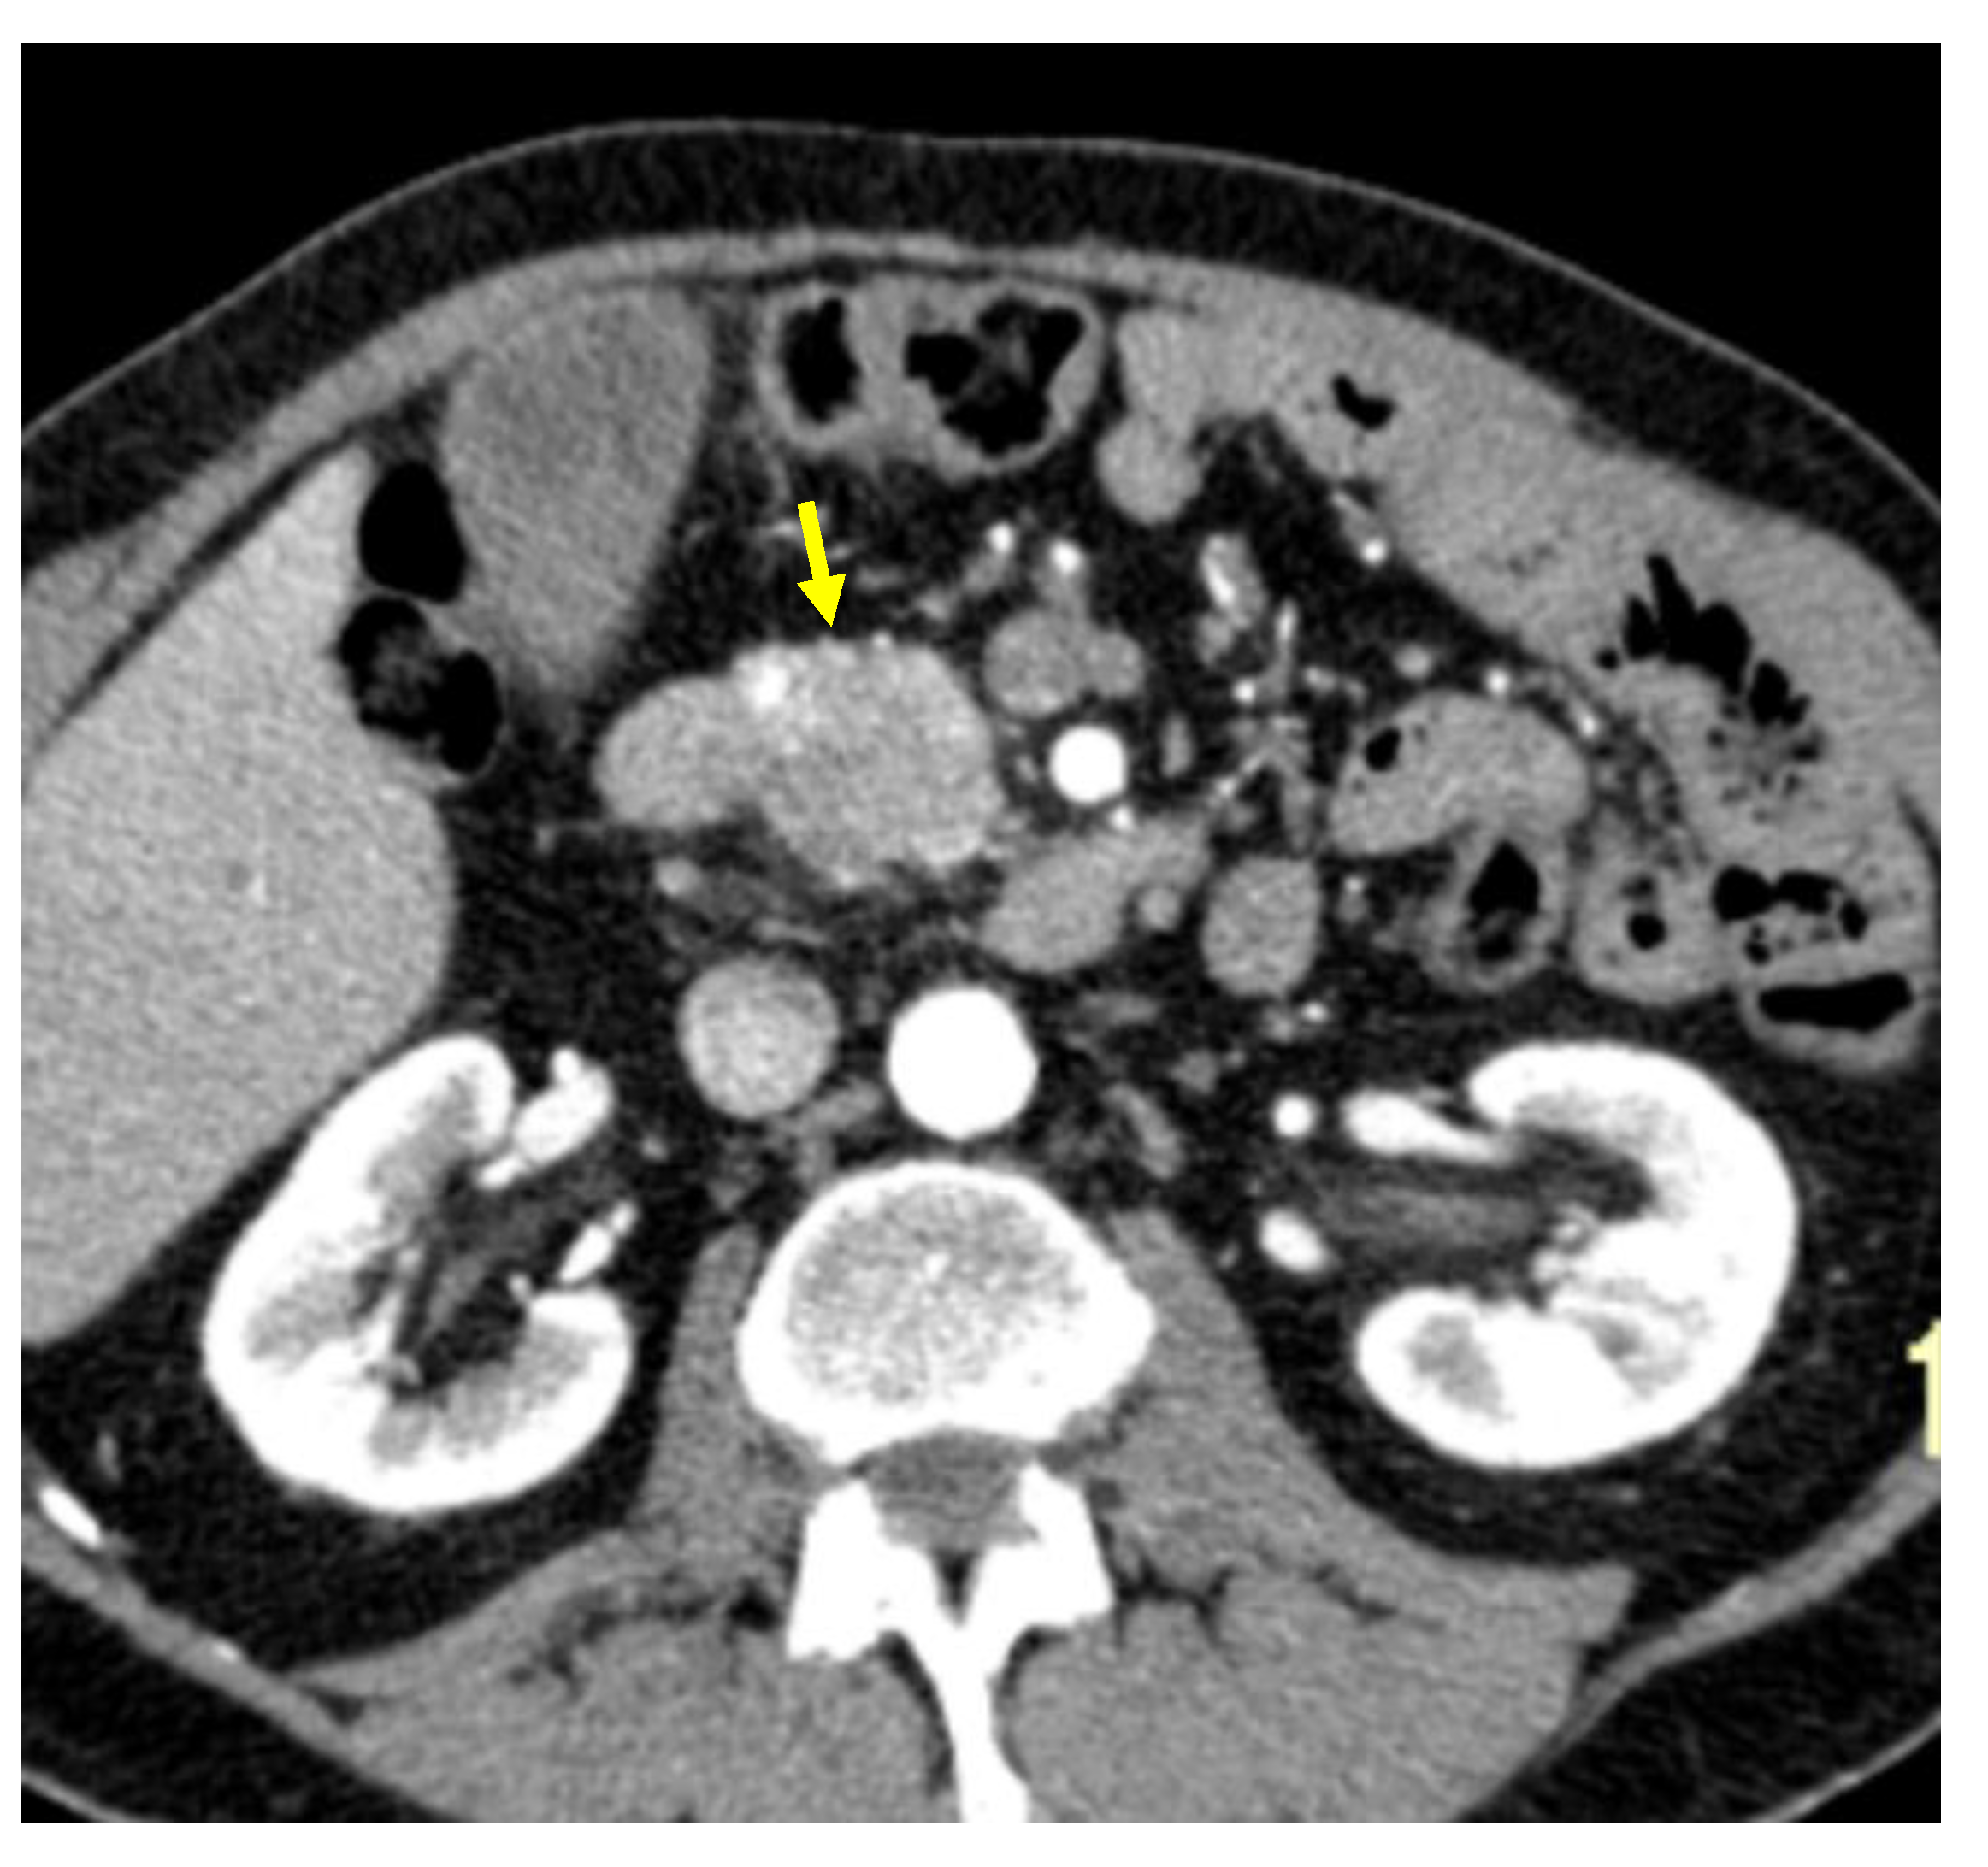

Tumor margins showed a significant difference in the two groups, appearing well-defined in only 6 (6.98%) metastatic patients and ill-defined in the remaining 80 (93.02%); in the non-metastatic group, the margins appeared well-defined in 132 (65.35%) and ill-defined in 70 (34.65%) tumors (Figure 2, Figure 3, Figure 4 and Figure 5).

Figure 2. Pancreatic lesion with well-defined margins (arrow) on CT examination in pancreatic contrast phase.